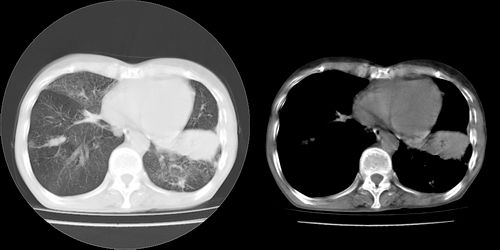

以下是引用lihuuuu在2006-7-18 18:16:00的发言:[br]支持肺结核诊断[br]本病例符合结核“三多”“三少”特征(多病灶、多形态、多钙化、少肿块、少堆积、少增强)中的前五个特征,另外左下叶背段有不张样改变-考虑伴有支气管内膜结核所致段不张。

以下是引用yang4132在2006-7-18 10:04:00的发言:[br]两肺多发 多形态病变,部分半纤维条索和斑点壮钙化,胸膜肥厚粘连,考虑结核。